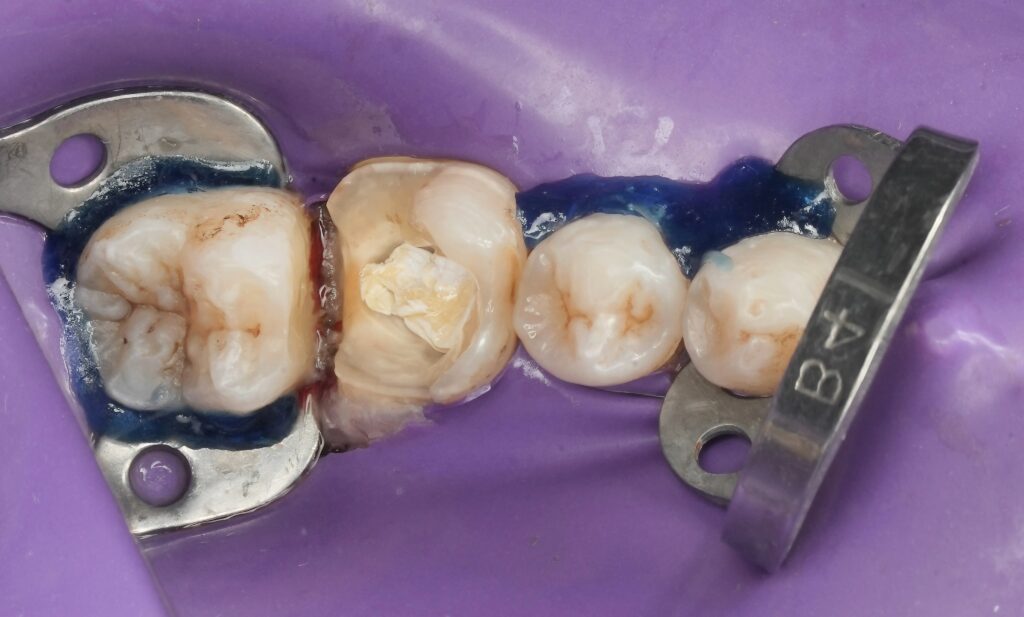

1. Rubber Dam Isolation

Strict isolation was achieved using clamp stabilization and liquid dam reinforcement.

6. Proximal Matrix Placement

A sectional matrix system was used with wedge adaptation to:

- Achieve tight contact

- Protect gingival tissues

- Control marginal emergence

Matrix precision is critical for periodontal stability.

7. Deep Margin Elevation (DME)

The deep distal margin was elevated coronally using incremental composite placement.

Protocol:

- Selective enamel etching

- Adhesive application

- Flowable composite base

- Layered composite build-up

The margin was relocated supragingivally, allowing ideal finishing and polishing.

DME allows preservation of tooth structure while avoiding surgical intervention (Dietschi & Spreafico, 1998).